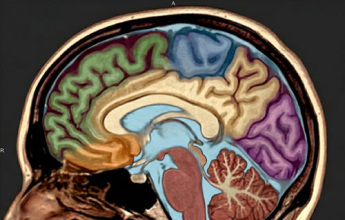

توصل فريق بحثي دولي إلى اكتشاف علمي قد يغيّر مستقبل علاج هشاشة العظام وفقدان الكتلة العظمية المرتبط بالتقدم في العمر، عبر تحديد بروتين يعمل كـ"مستشعر للتمارين الرياضية" داخل الجسم، ويمكن تنشيطه دوائيًا لمحاكاة فوائد النشاط البدني دون الحاجة إلى الحركة الفعلية.